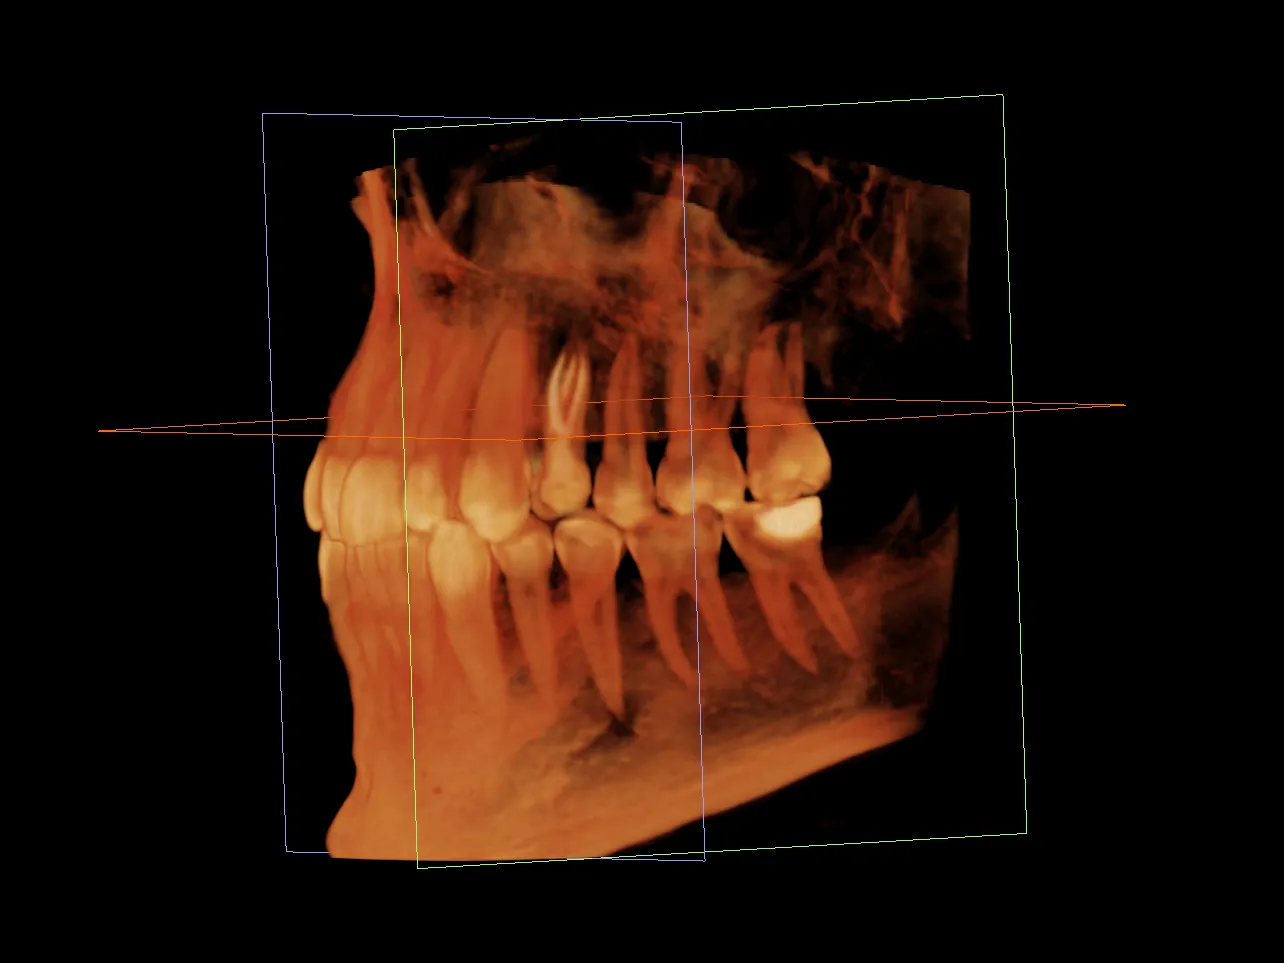

Rozpisane krok po kroku: na co zwrócić uwagę w diagnostyce radiologicznej i jakie ma ona odzwierciedlenie w rzeczywistości pod mikroskopem.